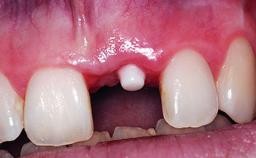

Replacement of an Upper Right Central Incisor with Root Resorption: Ridge Preservation, Early Placement of an RC Bone Level Implant

A 49-year-old female patient was referred for implant therapy to replace the upper right central incisor (tooth 11). The tooth had been assessed by an endodontist who diagnosed a vertical fracture of the root. The tooth had a hopeless prognosis and needed to be extracted. The patient was healthy and was not taking any medications. She was allergic to penicillin. The patient had high esthetic demands but her expectations were realistic. The extraoral examination revealed no facial asymmetries. The right temporomandibular joint demonstrated an opening click but was otherwise asymptomatic. The lip line was high with a significant gingival display.